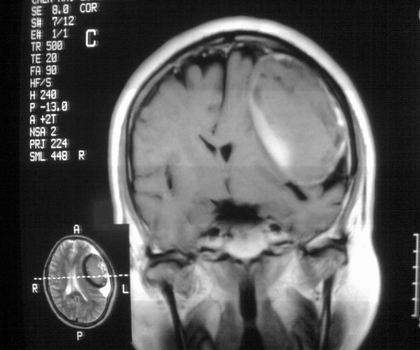

以下是引用影像孺子牛在2008-4-29 21:20:00的发言:[br]首先病变定位在脑外,根据ct密度及mri信号特征考虑慢性硬膜下血肿不连续环形钙化。

以下是引用周战梅在2008-4-29 23:12:00的发言:[br]脑外病变,蛛网膜下腔增宽,囊壁点状、环形钙化,增强扫描呈不均匀环状强化,考虑为囊性脑膜瘤可能性大,慢性脓肿、血肿机化、胆脂瘤不能除外。